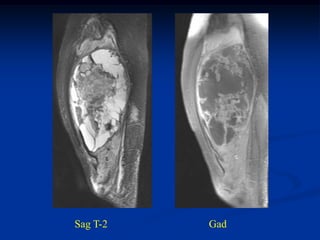

Case #250.3      Sag T-2                 Sag Gad

15 year female with painful enlarging desmoid past 6 months

while on chemotherapy

Coronal Gad shows minimal response to chemotherapy

Axial T-2

vessels

Axial Gad

Cor T-2        Two Cor gad              Sag gad

2 yrs later with recurrence above and below the RT ports

Prox thigh axial T-2   Gad

Distal thigh in area

of previous surgery

and 5000 rads RT